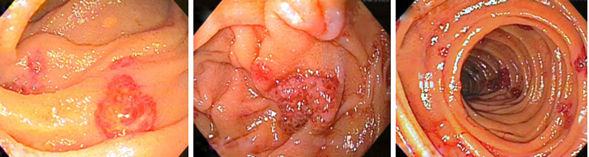

Gastroenterología lleva a nueva enteroscopia con balón anterógrada y retrograda, encontrando “innumerables lesiones nodulares sésiles eritemato-violáceas en estómago, duodeno, yeyuno, íleon y colon” (Figuras 1 a 3). Las biopsias tomadas de duodeno y estómago muestran “lámina propia infiltrada por células anaplásicas de tamaño variable, con figuras mitóticas abundantes y nucleolos prominentes, sin células en anillo de sello”, con lo que hacen diagnóstico de tumor maligno de origen linfoide versus sarcoma. Las pruebas para Herpes Virus Humano 8 (HHV8), herpes simple (HSV) 1 y 2, y citomegalovirus (CMV) fueron negativas en las células neoplásicas. En la citometría de flujo había disminución relativa de linfocitos T CD4 respecto a T CD8, sin expresión aberrante de linfocitos, y en la inmunohistoquímica, CK coctel negativa, CD30 positiva focal, CD31 positiva difusa, vimentina positiva difusa, con KI67 con índice de proliferación del 67 %, resto de panel de coloraciones especiales fueron negativas. El informe final inmunohistopatológico confirmó angiosarcoma intestinal.

En cuanto al diagnóstico, por ser la hemorragia digestiva la manifestación más común, los estudios endoscópicos serán la primera aproximación, con los cuales se podrá ver de manera directa lesiones polipoides de rojo a púrpura, hipervascularizadas, hemorrágicas, de consistencia blanda 10. Además, permiten la toma de biopsias, que mostrarán un epitelio hemorrágico y en ocasiones ulcerado, con formación de espacios vasculares tipo hendiduras, revestidos por células atípicas grandes, de forma redonda a poligonal, de citoplasma eosinofílico, con macronúcleos pleomórficos y con figuras mitóticas anormales.